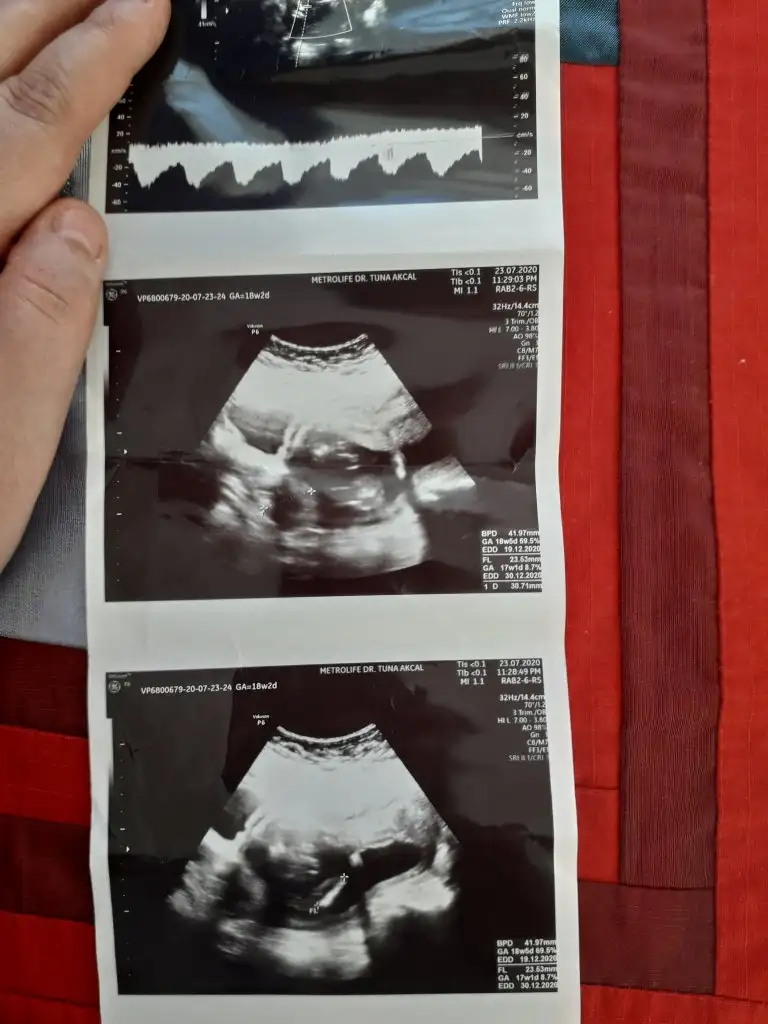

Nub olmaz bu haftalarda hayırlısıikra meyra canim kesemize erkek gibi demistin ,13 haftalik olana dr erkek dedi sen kiz gibi demistin tam net cikmamis ama dün kontrolum vardi 18haftaligiz dr kız gibide diyebilirim dedi yine netlesmedi cinsiyetimiz son usg den belli olmuyor dimi ?